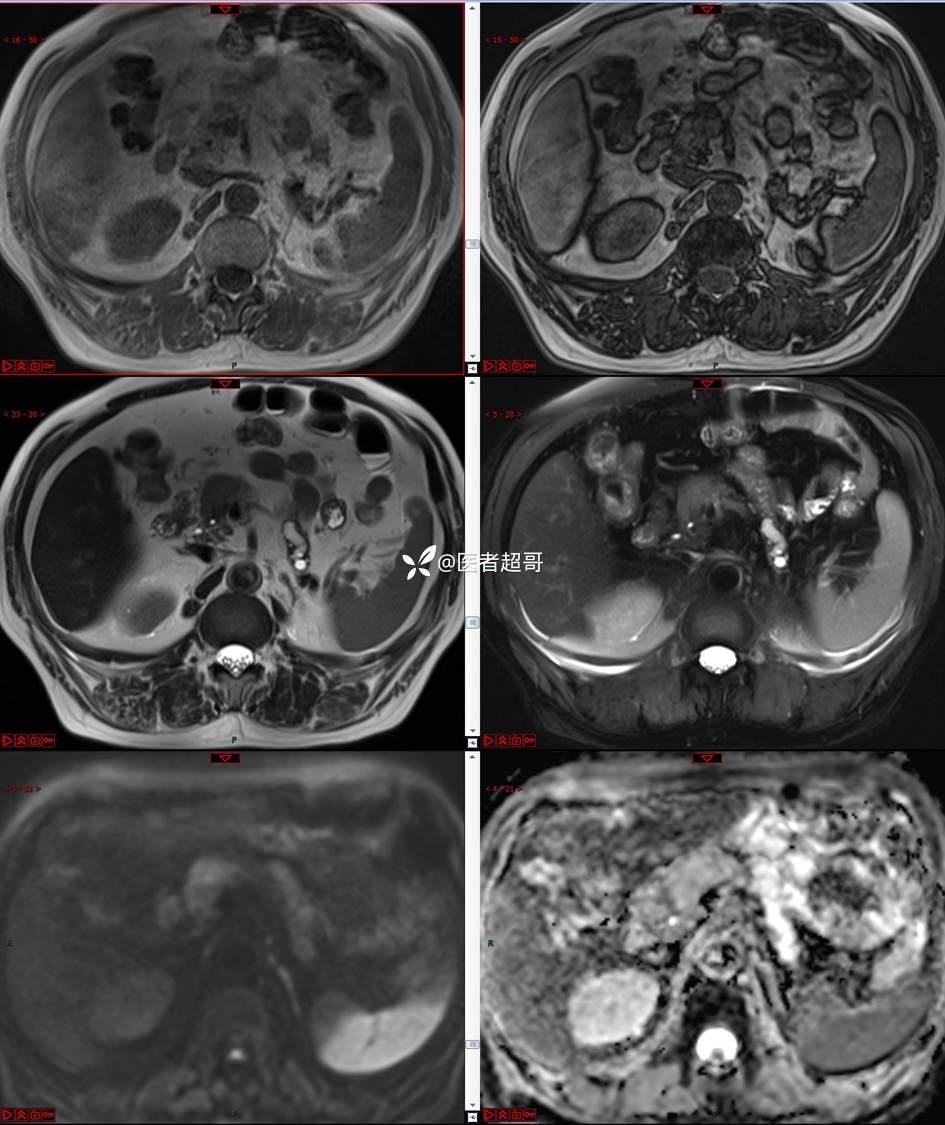

【影诊笔记677】查体发现胰腺占位性病变1周,细节决定成败,请诊断分析!

主 诉:查体发现胰腺占位性病变1周。

现病史:患者1周前在当地查体时发现胰腺占位性病变,无恶心、呕吐,无腹痛,无寒战、高热,无咳嗽、咳痰等异常不适,来我院门诊查上腹部CT平扫+强化:胰腺尾部异常密度灶。今为求进一步治疗,门诊以“胰腺占位性病变”收入院。患者自发病以来,一般情况可,神志清,精神可,普通饮食,二便正常,体重及体力无明显改变。

既往史:既往糖尿病病史2年,口服二甲双胍早晚各一片和格列吡嗪早晚各一片,否认高血压、心脑血管病等疾病史,否认肝炎、结核或其他传染病史及密切接触史,预防接种史不详,否认药物及食物过敏史,否认外伤史,12年前肾癌切除术手术史,否认输血史,其它无特殊。